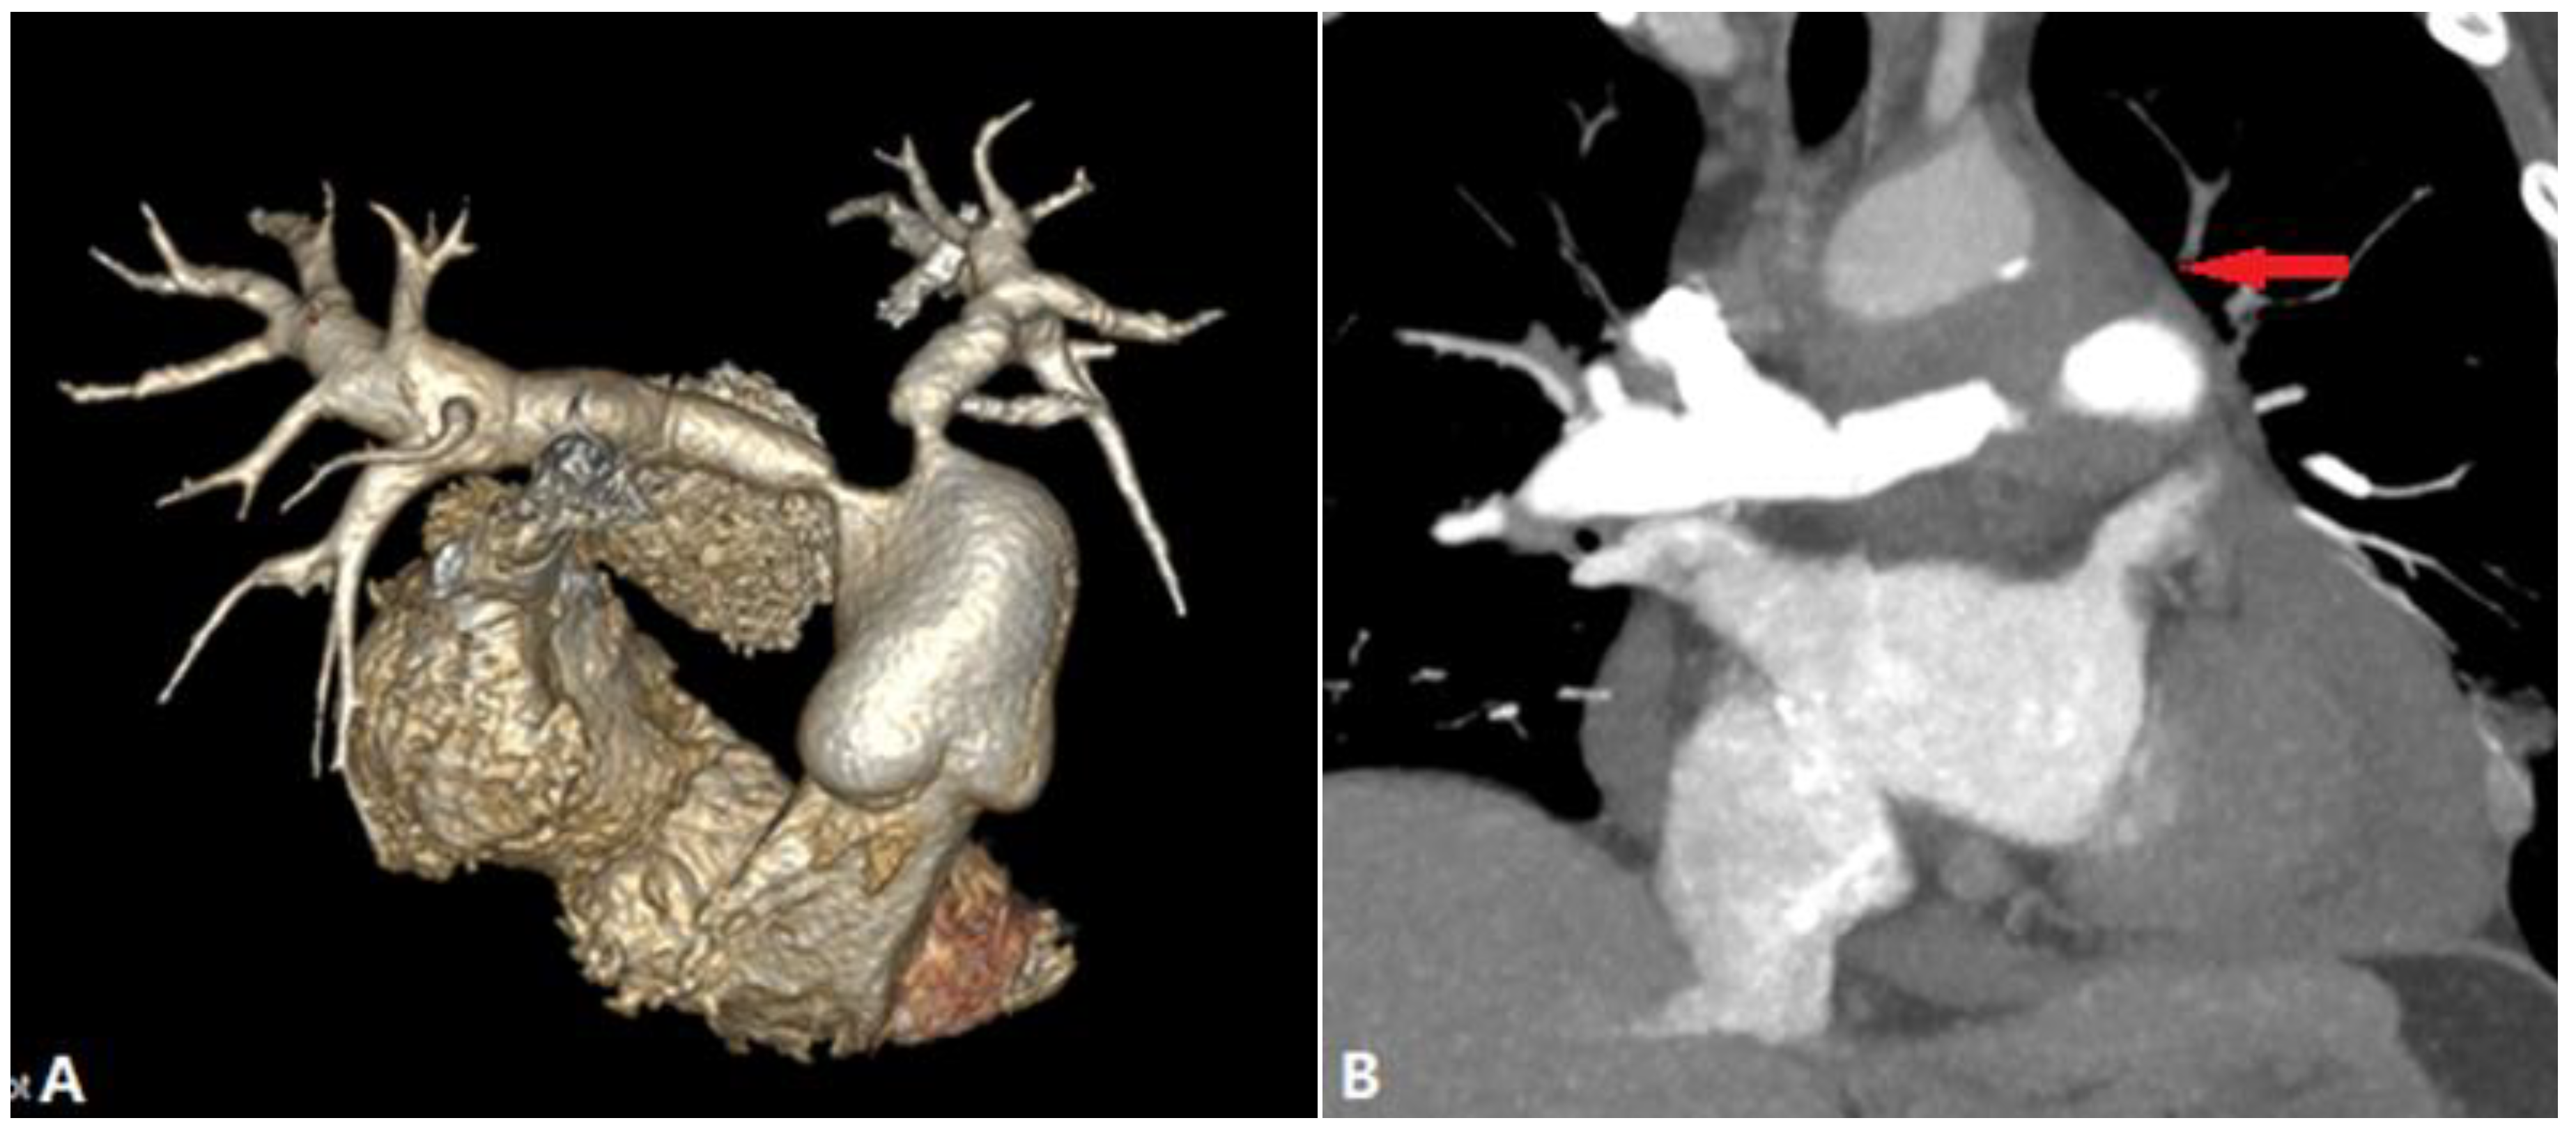

4.1.6. Pulmonary Artery Sarcoma

4.2. Vessel Wall Lesions